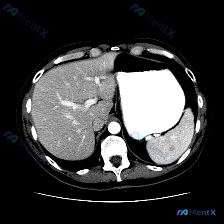

整理了一个很有意思的读片资料,先看一下基本情况: 影像资料概况 - 扫描部位:上腹部横断面CT(软组织窗) - 图像质量:清晰,对比度适中,无明显运动伪影 - 显示结构:肝脏、胃、脾脏、腹主动脉、椎体及周围软组织 主要影像描述(按器官整理) - 肝脏:形态轮廓尚平滑,实质密度均匀,未见明显局限性肿块...

看到一个很有意思的影像分析案例,整理了一下思路和大家分享: --- 【先看影像分析的客观结果】 这是一幅腹部增强CT横断面图像(腹主动脉内见高密度对比剂充盈,提示动脉期或血管期)。 影像所见: - 脾脏:形态大小正常,无肿大;脾实质密度均匀,未见明确占位、梗死灶或局灶性强化异常。 - 其他结构:双侧...

整理了一份挺有意思的影像分析资料,和大家聊聊思路。 病例/影像背景 临床预设存在“脾脏病变”,提供了一张腹部CT横断面(软组织窗)图像。 影像核心观察 我先把图像里的关键信息理一理: 1. 脾脏本身:左侧脾脏形态、大小、实质密度都大致正常,没有看到局灶性的低密度或高密度影,边缘也光滑 2. 其他腹部...